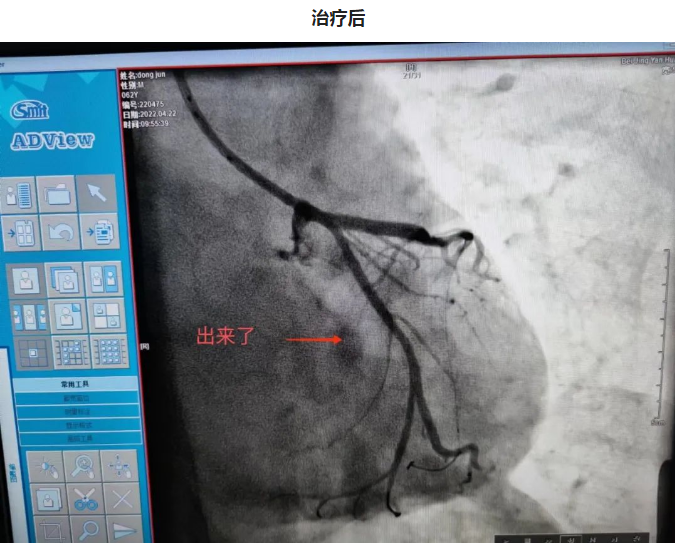

第二日晨,3年前冠脉置入一枚支架的62岁的董大爷干农活时突发咽部紧缩感,伴胸闷不适,持续不缓解,呼叫120送至我院急诊,血压75/56mmHg,急诊考虑急性下壁心肌梗死,心源性休克,急诊立即排查新冠肺炎的同时联系我科,做好术前准备后急送至导管室,冠脉造影可见原支架位于左主干至前降支近段,回旋支消失不见,李钢主任反复尝试后找到回旋支开口,并给予成功重新开通血管,患者血流恢复,症状缓解,但血压持续偏低,考虑患者心源性休克,给予患者置入IABP(主动脉内球囊反搏)作为辅助,患者心功能逐渐恢复,治愈出院。